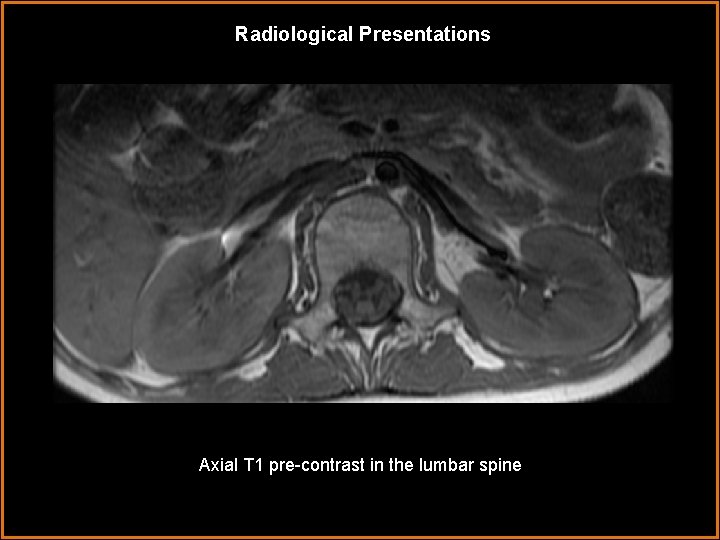

Radiological Presentations Axial T 1 pre-contrast in the lumbar spine =

Radiological Presentations Axial T 1 pre-contrast in the lumbar spine

Findings and Differentials Findings: The dorsal and ventral nerve roots are enhancing throughout the cervical, thoracic, and lumbar spine. There is avid contrast enhancement and thickening of the cauda equina nerve roots, both in their intrathecal and extraforaminal segments. The spinal cord is not enhancing. Incidental note Differentials: is made • Guillain-Barré syndrome • Miller-Fisher syndrome • Leptomeningeal carcinomatosis • Spinal meningitis of left lower lobe atelectasis.